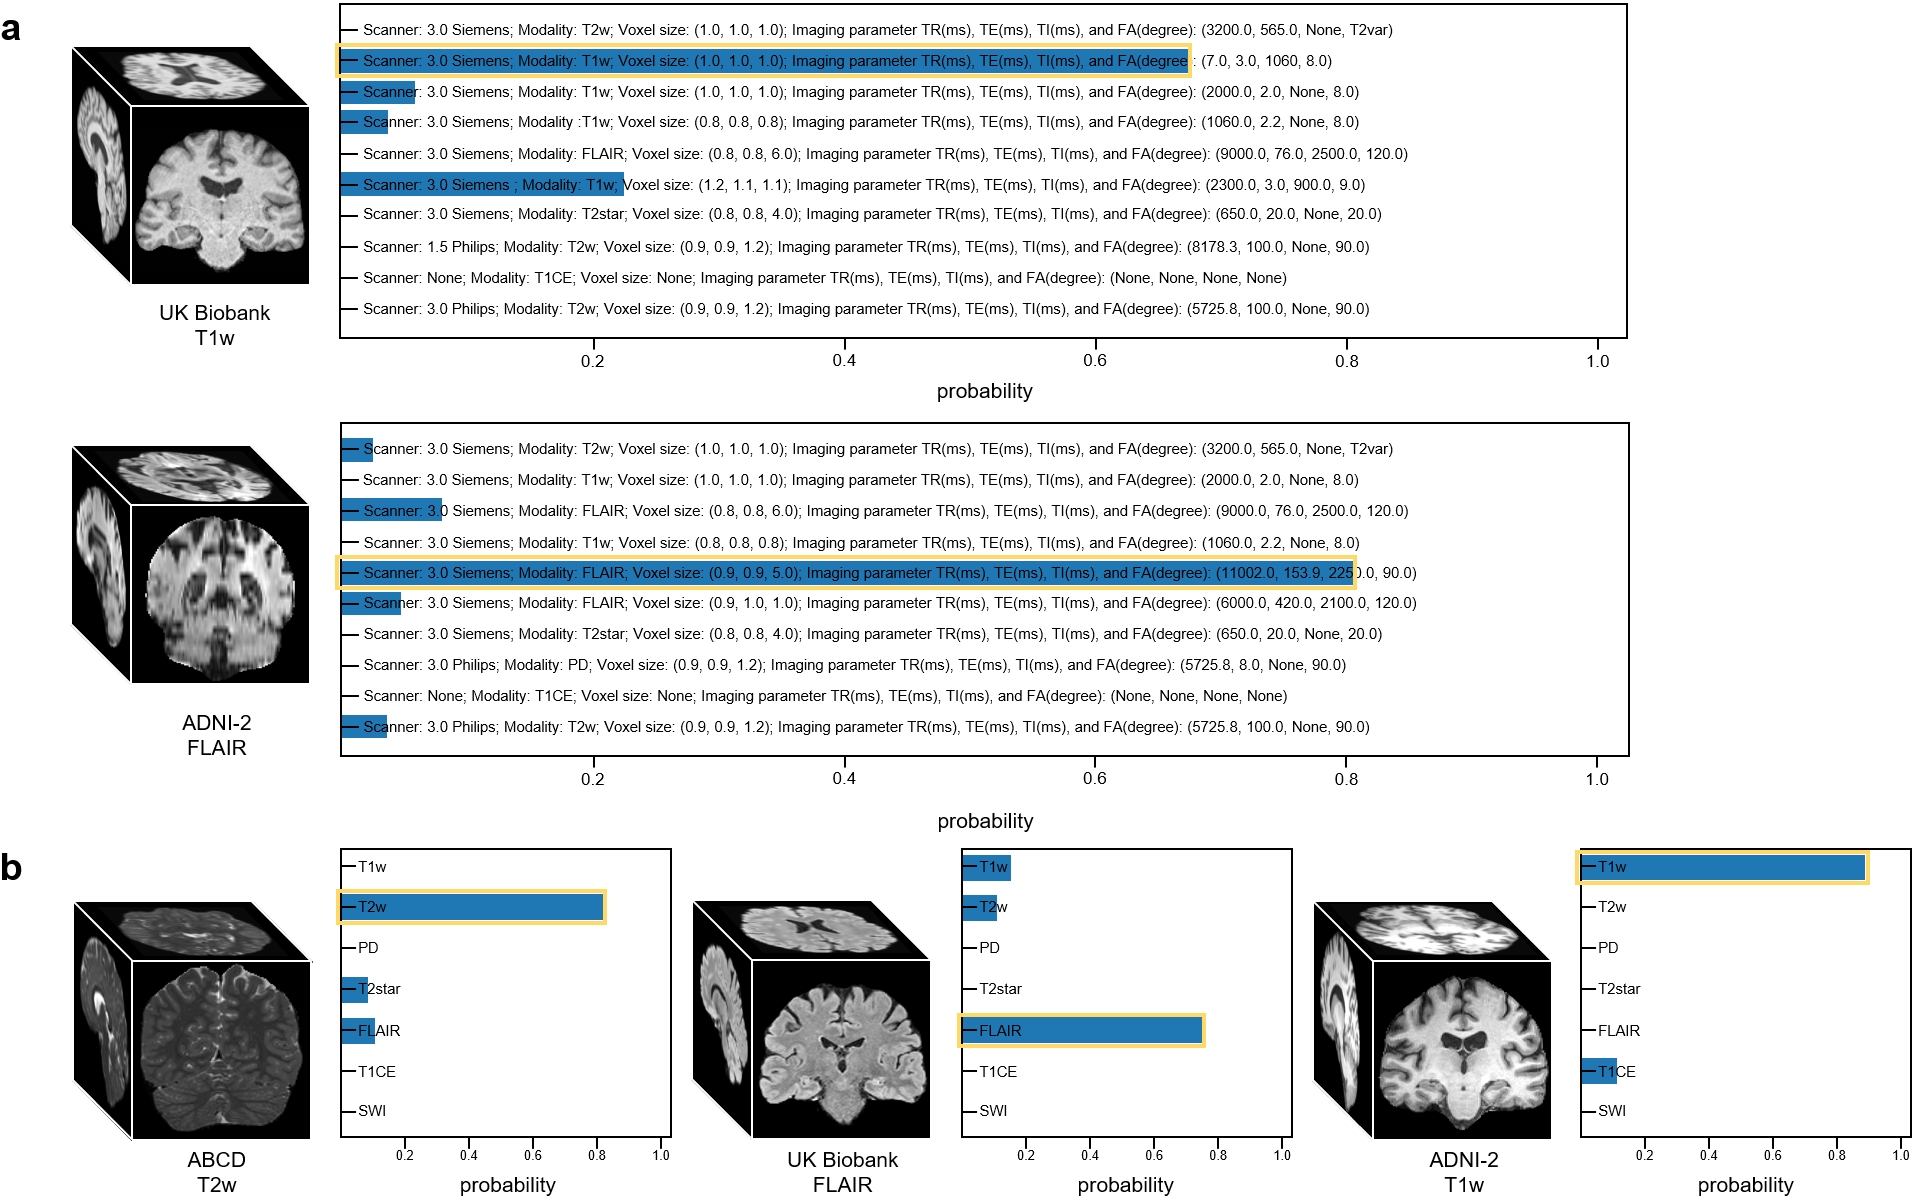

The overview of our work is shown in Fig.1. The goal of our work is to develop a universal synthesis framework for brain MR images, which can generate desired high-quality MR images according to practical demands provided by text prompts. To ensure the versatility and generalizability of our synthesis model, we collected a large-scale brain MR database with 31,407 3D image-text pairs from 13 datasets located in four continents, including 7 structural MRI modalities, spanning ages from 2 to 100+ years old, and covering a large spectrum of diseases and health conditions (Table 1). The text (metadata) includes subject information such as age and gender, as well as key MR imaging parameters, including scanning field strength, scanner type, voxel size, repetition time (TR), echo time (TE), inversion time (TI), and flip angle (FA). The designed English prompt integrates metadata as illustrated in Fig.1 b and c. To effectively align and fuse image-text pairs, our TUMSyn is built upon a two-stage training strategy. In the first stage, we pre-trained a text encoder using contrastive learning to effectively extract textual semantic features which are aligned with the corresponding image features from metadata (Fig.1 b). In Supplementary Fig.1 a and b, we evaluate the pre-trained text encoder by showing zero-shot performance on image-to-text retrieval. We can see that our text encoder accurately provides highly relevant textual descriptions for the given images, either producing complete prompts or solely imaging modality, indicating its ability to understand and master the semantic relationship between paired images and texts. More details are given in section “Description of experimental setup”.

Evaluation of pretrained text encoder through image-to-text and image-to-modality retrieval